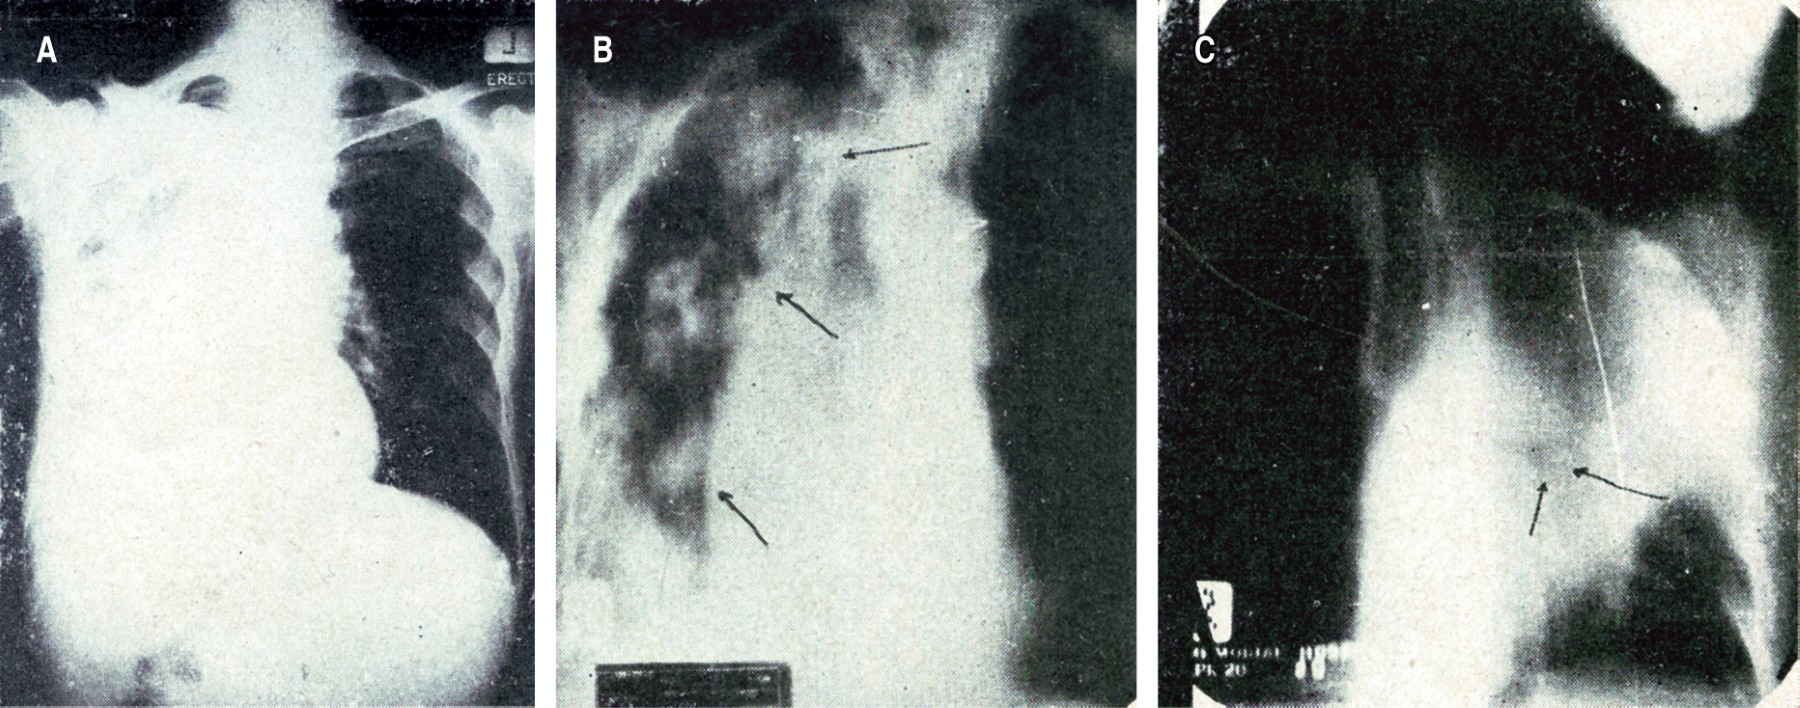

Poco después, en 1946, el Dr. Nicolás Amerena publicó en NCT su artículo "Estudio del diagnóstico radiológico del cáncer de pulmón".4 En éste, describió tres formas anatomopatológicas fundamentales: tumor de la pared del bronquio cerca de hilio, forma difusa infiltrante y cáncer lobular con nódulos carcinomatosos intralobares, además de algunas otras variedades como el tumor de grandes nódulos y los tumores que dan lugar al desarrollo de la llamada linfangitis carcinomatosa. Dentro de las manifestaciones secundarias diagnosticadas radiológicamente estaban los derrames pleurales, atelectasias o infiltraciones neumónicas, cavitaciones de los tumores y parálisis del diafragma por compresión del nervio frénico con mayor frecuencia en tumores del lado derecho. El Dr. Amerena se enfocó a la broncografía y comentaba que, en caso de que se sospeche de una afección neoplásica, este estudio era el que estaba indicado, complementándolo con la broncoscopia. Las imágenes broncográficas que describió fueron de tres tipos: lagunas o defectos marginales, desfiladeros bronquiales y obstrucciones totales. Siendo encontradas en diversas situaciones de los tumores bronquiales; las primeras cuando había lesiones bronquiales de tipo infiltrativo, las segundas si había evidencia inicial de obstrucción con dilataciones posestenóticas; y la tercera si había una atelectasia masiva del pulmón afectado.